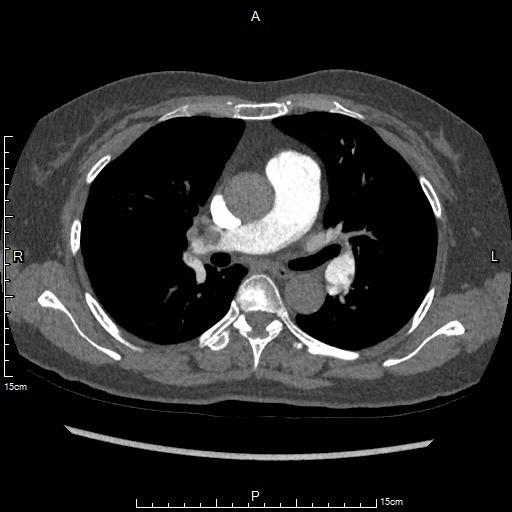

老年女性,行脑血管动脉造影术后,如厕后突发晕厥,行急诊肺动脉CTA检查提示双侧肺动脉多发栓塞。心脏彩超显示中-重度肺动脉高压。下肢静脉彩超提示右侧胫后静脉及肌间静脉血栓形成,右股静脉血流缓慢。综合考虑为急性肺动脉栓塞。近期脑血管造影提示静脉畸形,颅脑MRI显示颅内陈旧性出血灶,静脉溶栓导致出血风险性较大。

大面积肺动脉栓塞